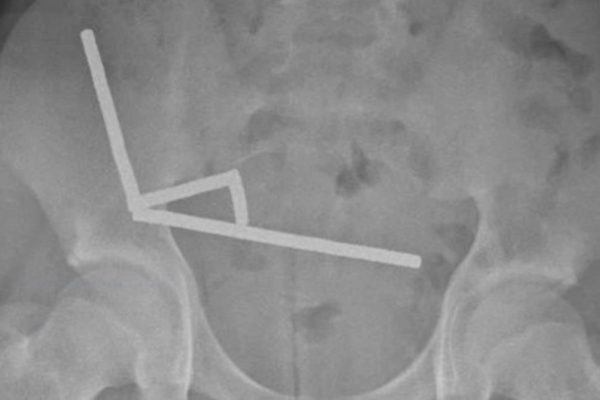

Noua abordare, descrisă într-un studiu realizat de cercetătorii de la Universitatea Flinders din Australia, se bazează pe un tratament existent numit stimulare nervoasă hipoglosală (HNS). Nervul hipoglos controlează limba, iar HNS folosește impulsuri electrice pentru a preveni blocarea gâtului de către limbă. Cu toate acestea, așa cum stau lucrurile în prezent, HNS necesită o intervenție…